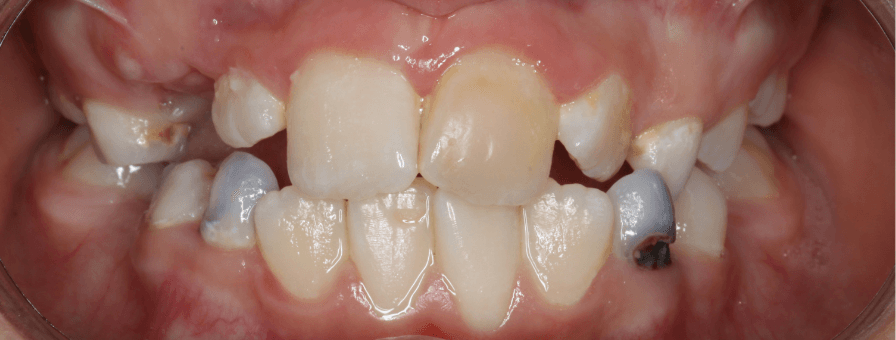

Tratament Interceptiv și Ortodonție Fixă - Dentiție Mixtă

Aceasta este o pacientă de 9 ani pe care am tratat-o în două etape pentru a obține rezultate optime. În prima fază am aplicat tratament interceptiv specializat pentru copii, folosind un disjunctor pentru expansiunea arcadei superioare. Ulterior, am continuat cu aparat fix bimaxilar pentru alinierea perfectă și corectarea mușcăturii.